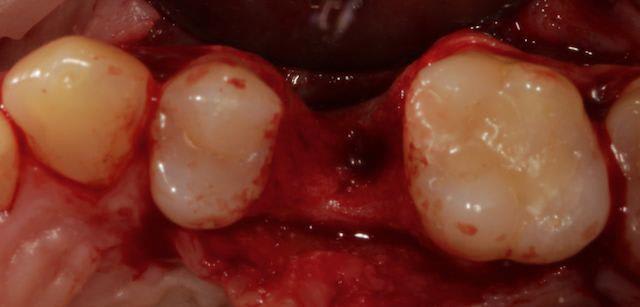

Cas 1-coté gauche maintenant:

1- ouverture, forme et configuration différente

2- une fois échauffée avec le coté droit, je me dis allez hop, j'attaque une expansion. donc incision crestale avec décharges osseuses

3- mise en place des expanseurs de Mesinger A et B

4-5 notez que l'incision de décharge étant oblique , elle sert également de garde fou contre une éventuelle fracture osseuse. l'os "mobile" vient buter contre l'os "immobile"

la suite en primeur pour ceux qui viennent à Sallanches les 28 et 29 Mars...